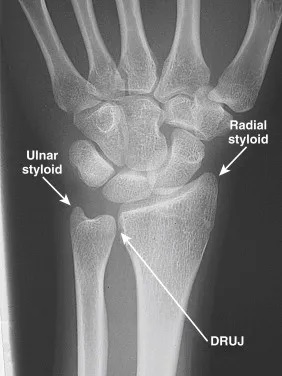

Distal radioulnar joint dislocation is an uncommon injury where the distal radius and ulna lose alignment, often caused by trauma, falls, or sports injuries. Patients typically present with wrist pain, swelling, deformity, and difficulty rotating the forearm. Diagnosis is made

A TFCC tear refers to injury of the triangular fibrocartilage complex, a key stabilizer of the distal radioulnar joint and ulnar side of the wrist. Tears can occur from acute trauma, such as a fall on an outstretched hand, or from chronic repetitive loading, particularly with

The DRUJ compression test evaluates for pathology at the distal radioulnar joint. With the forearm in a neutral position, the examiner compresses the ulna against the radius. The test evaluates for instability, tenderness, crepitus, or swelling and is compared to the